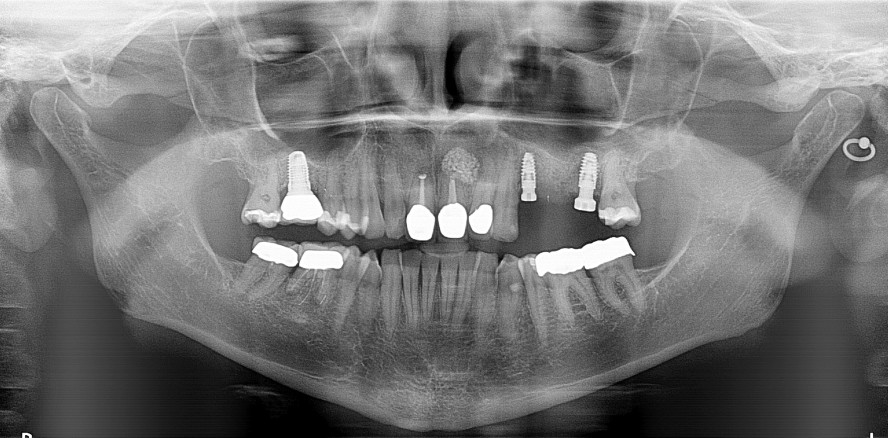

Bei der Röntgenkontrolle nach einem Jahr sieht man den Erhalt des Knochens an 26 apikal sowie die Stabilität des Hartgewebes krestal an beiden Implantaten, dies ist dem Platform Switching zu verdanken. Einerseits durch mehr Knochen krestal und andererseits durch die konkaven Komponenten werden die Voraussetzungen für langfristige Stabilität und ein gesundes periimplantäres Gewebe erschaffen (Abb. 13). Der krestale Knochen wird zusätzlich durch eine Zahnfleischmanschette um das konkave Abutment geschützt.